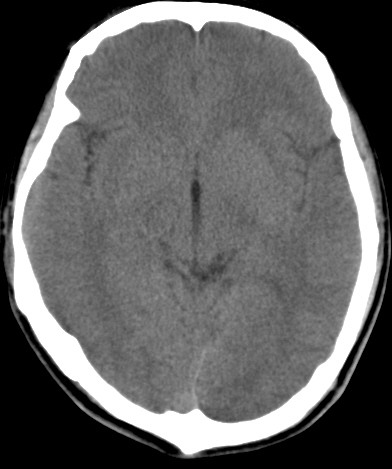

男,31岁,头疼就诊,其他不祥。

考虑右颞叶脑血管畸形伴出血。avm可能大,建议dsa。

平扫见右颞叶、右侧脑室后角旁略高密度影,增强未见明显病灶,基本正常。不放心做mri检查

病灶呈略高密度,周围伴环形水肿,无强化/无异常av影........

考虑为:1.脑内小血肿?   2.脑灰质异位?   建议mri检查........

考虑右颞叶脑血管畸形伴出血。考虑静脉血管瘤,深部型的,avm不除外,建议dsa。